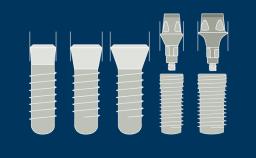

This module will define risk factors, both systemic and local, in relation to implant therapy as well as relative and absolute contraindications to implant placement.

- identify risk factors associated with implant therapy

- identify the local risk factors associated with implant therapy